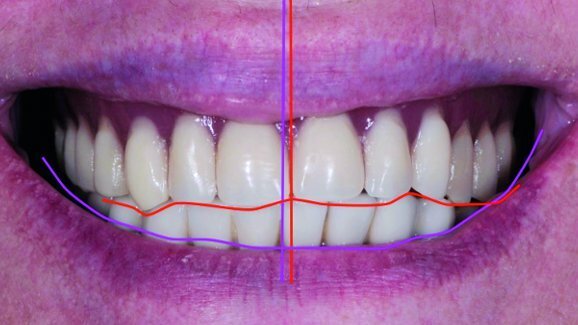

In our case, a 58-year-old patient presented at the practice with discomfort caused by her complete maxillary denture. When looking at her history, we found a prosthetic restoration retained on six im plants in the lower jaw and a complete maxillary denture that was aesthetically and functionally inadequate (Fig. 1). An initial aesthetic evaluation established that the shape and shade of the teeth were inappropriate. In addition, the midline was misaligned and the curvature of the maxillary anterior teeth was shaped incorrectly.

In order to proceed to the next stage of the treatment, we required a functional impression that would transfer the exact position of the implants. For this purpose, the four impression posts were splinted together on a custom tray with composite material (Figs. 2 & 3). After creating the working models (Fig. 4), we determined the patient’s vertical dimension of occlusion, the length of the future teeth, as well as the gingival smile line, by means of an occlusal plate (bite rim). In the upper jaw, the occlusal rim was shaped in such a way that 2 mm of the edge was visible when the upper lip was in rest position. The lower edge of the rim was aligned parallel to the bipupillary plane and smoothly followed the curve of the lower lip when the patient smiled. On the maxillary rim, the midline, the smile line and the line of the canines were outlined. A facebow was used for the transfer of the maxillary position in relation to the base of the skull.